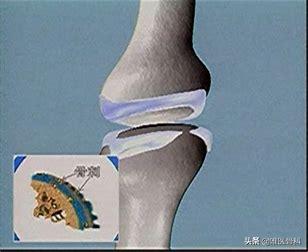

虽然,骨关节炎的疼痛表现在关节,但究其病因其实在关节表面覆盖的一层软骨。当人步入中年以后,人体各脏器开始衰老,软骨自然也不可避免地发生退化。我们对于膝关节骨关节炎其实已经比较了解了,我们就以膝关节骨关节炎为例,软骨就像是覆盖在真正的骨(胫骨、股骨、髌骨等)表面的一层保护套,软骨的性能优良,可以承担我们在日常生活中出现的膝关节磨损、冲撞、震荡等等,就好像机器运行过程中的减震垫和耐磨垫一样。而随着时间的推移,软骨的自身性能因为衰老等因素出现的降低,此外经年累月的磨损和冲击也导致软骨层越来越薄,最终出现了软骨完全磨穿,真正的骨与骨发生摩擦,由于真正的骨表面的骨膜下神经的存在,疼痛就成为了膝关节骨关节炎最为直接和明显的症状表现。

骨质增生常常是骨关节炎的表现之一